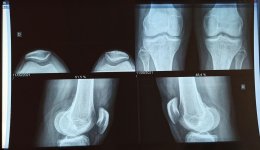

ألم تحت الصابونة و في جوانبها عند الوقوف عند ثني الركبتين و عند الصعود على درج حرقان في الركبتين تحت الصابونة بالضبط ابتداء منها ونزولا الى القدمين .. صعوبة في المشي طويلا و عند الصعود لمكان عالي .. ليس عندي حرارة موضعية أو تورم

- قال لي عندك ميلان للصابونة عن مكانها قليلا